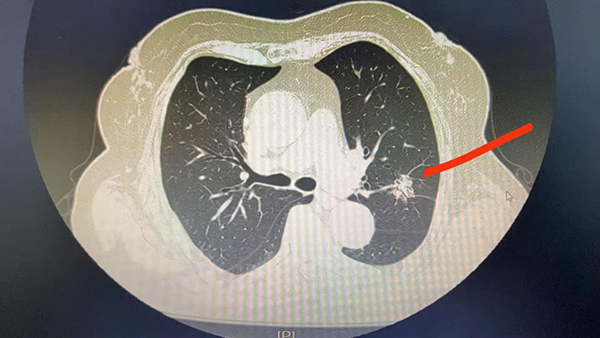

80岁的邵奶奶家住沈阳市铁西区,今年6月中旬,她来到市五院胸外科门诊进行双肺CT常规检查。检查结果显示,其左肺上叶存在一直径约2厘米的实性结节,形态不规则,边缘呈毛刺状,是典型的肺癌影像学改变。通常情况下,手术是此类病症的首选治疗方案,但邵奶奶的病灶位置较深,无法实施肺楔形切除术,只能进行左肺上叶全切手术。

考虑到邵奶奶年事已高,接受这样的大型手术存在一定风险,且术后肺功能会明显下降。胸外科团队经过全面评估与深入讨论,为邵奶奶制定了更为适宜的治疗方案——肺结节微波消融手术。该手术只需在局部麻醉下即可开展。6月30日,在完善的术前准备后,胸外科团队为邵奶奶实施了局部麻醉下的微波消融手术。手术过程顺利,仅耗时1小时。术后第二天复查双肺CT,未发现液气胸等异常情况。术后第三天,邵奶奶恢复良好,顺利出院。